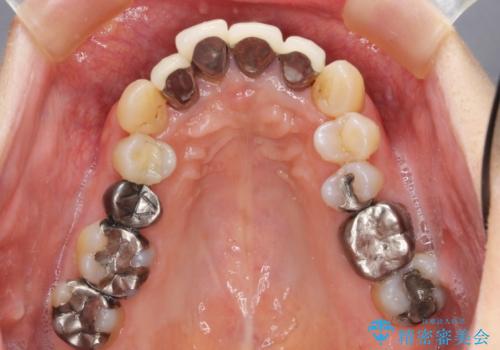

- 前歯の見た目・歯並び・銀歯の見た目の改善を求めて来院されました。

まずガタ付きの強い歯並びをマウスピース矯正インビザラインで整えたのち、セラミック治療による審美性の改善を計画します。

矯正治療が終わったのちに、精度の高いセラミックを装着することでより安定した噛み合わせとなり審美性も兼ね備えた口腔内状態で治療を終了し、今後のメンテナンスを行っていくことができます。